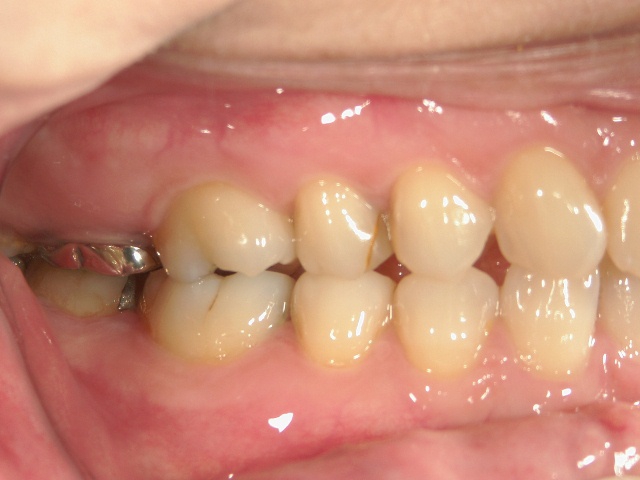

矯正歯科 治療前

矯正歯科(全顎ワイヤー矯正)治療後

全顎ワイヤー矯正 症例(2)

36歳女性 磐田市

在住

治療期間2年6

ヶ月